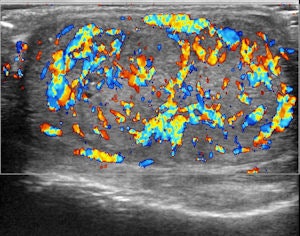

Top left: Grayscale ultrasound image of the testes showing a large isoechoic nodule (40 x 20 mm) compared with the testicular tissue (arrows). Top right: Color Doppler showing peripheral and central vascularization of the nodule, suggesting a malignant lesion. Bottom left: RTE of the nodule showing a large central strain area (mainly an intermediate elastic pattern displayed in green) (*) surrounded by a no-strain rim (the peripheral part of the lesion is blue) (arrows). This pattern, that the researchers suggested calling "score 3-inverted" (the opposite of the known color-coded score 3 reference of Itoh et al) seems to be related to the Leydig tumors. Bottom right: Gross specimen of the testicle. Histological diagnosis of the nodule was Leydig tumor, consisting of cells with abundant cytoplasm without interstitial fibrous stroma; the slow growth of the tumor induces sclerohyalinosis at the periphery. The tumor's macrostructure explains the RTE pattern.Because clinical examination has its drawbacks, ultrasound has become the imaging technique of choice for evaluating scrotal abnormalities -- with the primary function of ultrasound being the diagnosis of a testicular mass to distinguish intratesticular from extratesticular location. Most extratesticular masses are benign, but intratesticular ones are malignant.